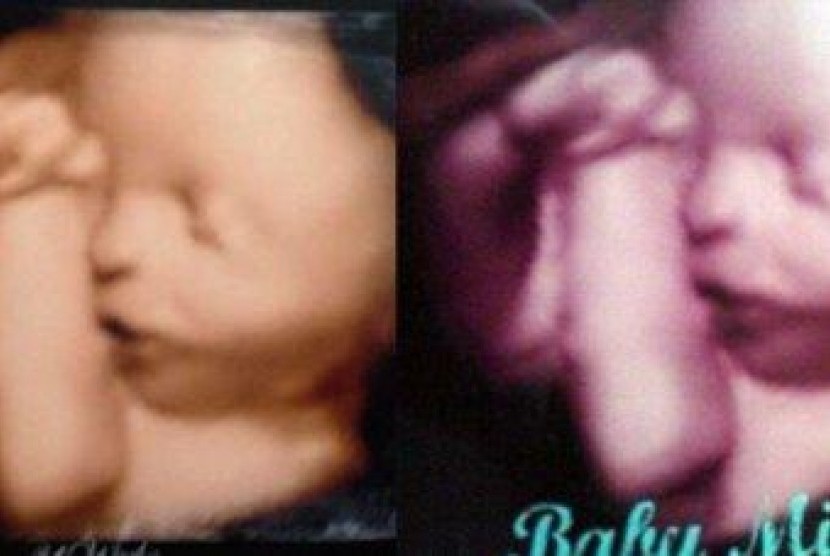

REPUBLIKA.CO.ID, AUSTRALIA -- Lembaga perlindungan konsumen di Australia Barat tengah menyelidiki keluhan dari sejumlah wanita di Bunbury yang mengklaim menerima foto USG janin palsu dari operator layanan foto USG di kota tersebut. Para korban baru mengetahui penipuan itu setelah mengetahui kalau foto USG yang diberikan operator hanyalah foto generik yang bisa ditemukan dengan mudah di internet.

Penyelidikan ini bermula ketika sejumlah wanita menyadari mereka telah menerima foto USG palsu setelah mereka mengunggah hasil scan foto USG janin di perut mereka yang didapat dari sebuah operator foto USG di sebuah rumah di Bunbury. Salah seorang korban bernama Catherin Osment, curiga ketika foto yang diberikan sangat berbeda dengan gambar yang ditampilkan langsung di alat USG maupun DVD. Osment juga mendapati semua nomor seri dan nama dibalik foto yang diprint oleh sang operator sangat berbeda.

Dan ternyata postingannya mendapat banyak respons dari kalangan wanita, yang kemudian ramai-ramai menggunggah foto USG mereka. Dari sini semua menjadi jelas kalau banyak diantara foto-foto itu yang sama persis."Saya sangat kecewa, tidak hanya untuk diri saya sendiri tapi juga bagi orang lain,” kata Osment.